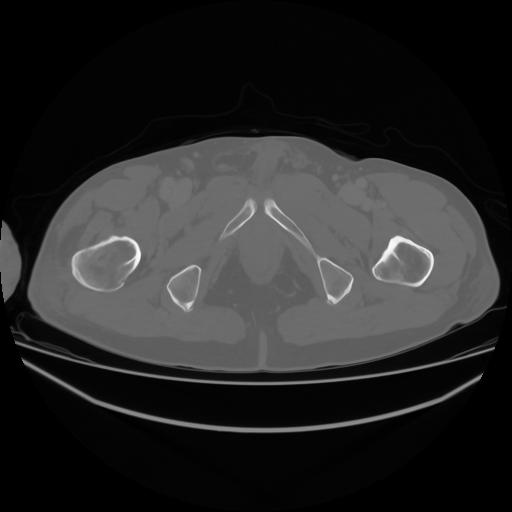

4 CUERPO,CE,Axial,3.0,CUERPO,,